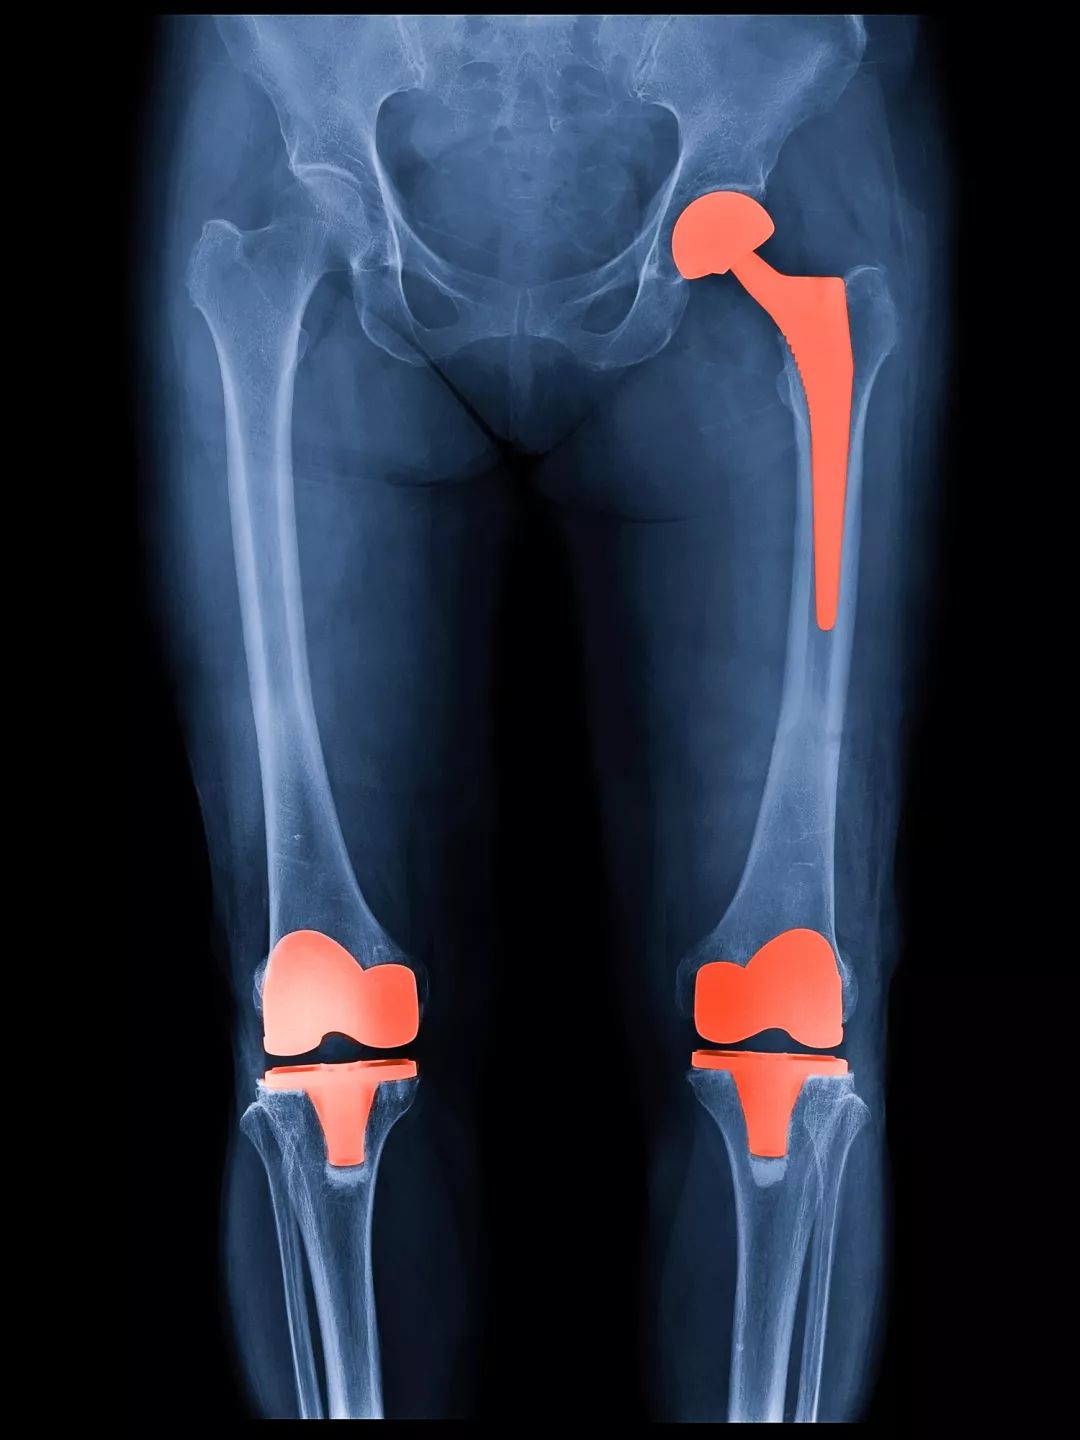

修复性治疗:包括目前还在研究中的软骨修复技术,以及应用比较广泛的胫骨高位截骨矫正力线等手术方式。

重建性手术:人工关节置换手术。包括全膝置换、单髁置换、髌股关节置换等。

在二三十年前,关节炎不管发展到什么严重的程度,都只能靠吃止痛药来忍着。逐渐丧失劳动能力,行走功能甚至生活能力;有些患者因为疼痛难忍,最终做了膝关节融合,甚至是截肢。

自上世纪八十年代前北大人民医院吕厚山院长将膝关节置换术引入国内以来,经过几十年的发展,目前这项技术已经非常成熟,全国每年光膝关节置换就要开展数十万例,成功案例不胜枚举。关节置换术也被誉为上世纪最伟大的三大医疗技术发明之一,成功解决了各种终末期关节炎、晚期股骨头坏死等原本无法解决的医疗难题。

所以说,有这种既好用又成熟的技术,并且自己的病也发展到了这一步,经济和身体允许的话,为什么不用呢?

当然,置换的关节假体是有使用寿命的,如果年龄较年轻,比如低于55岁,甚至是50岁,需要详细的评估利弊,再做选择。